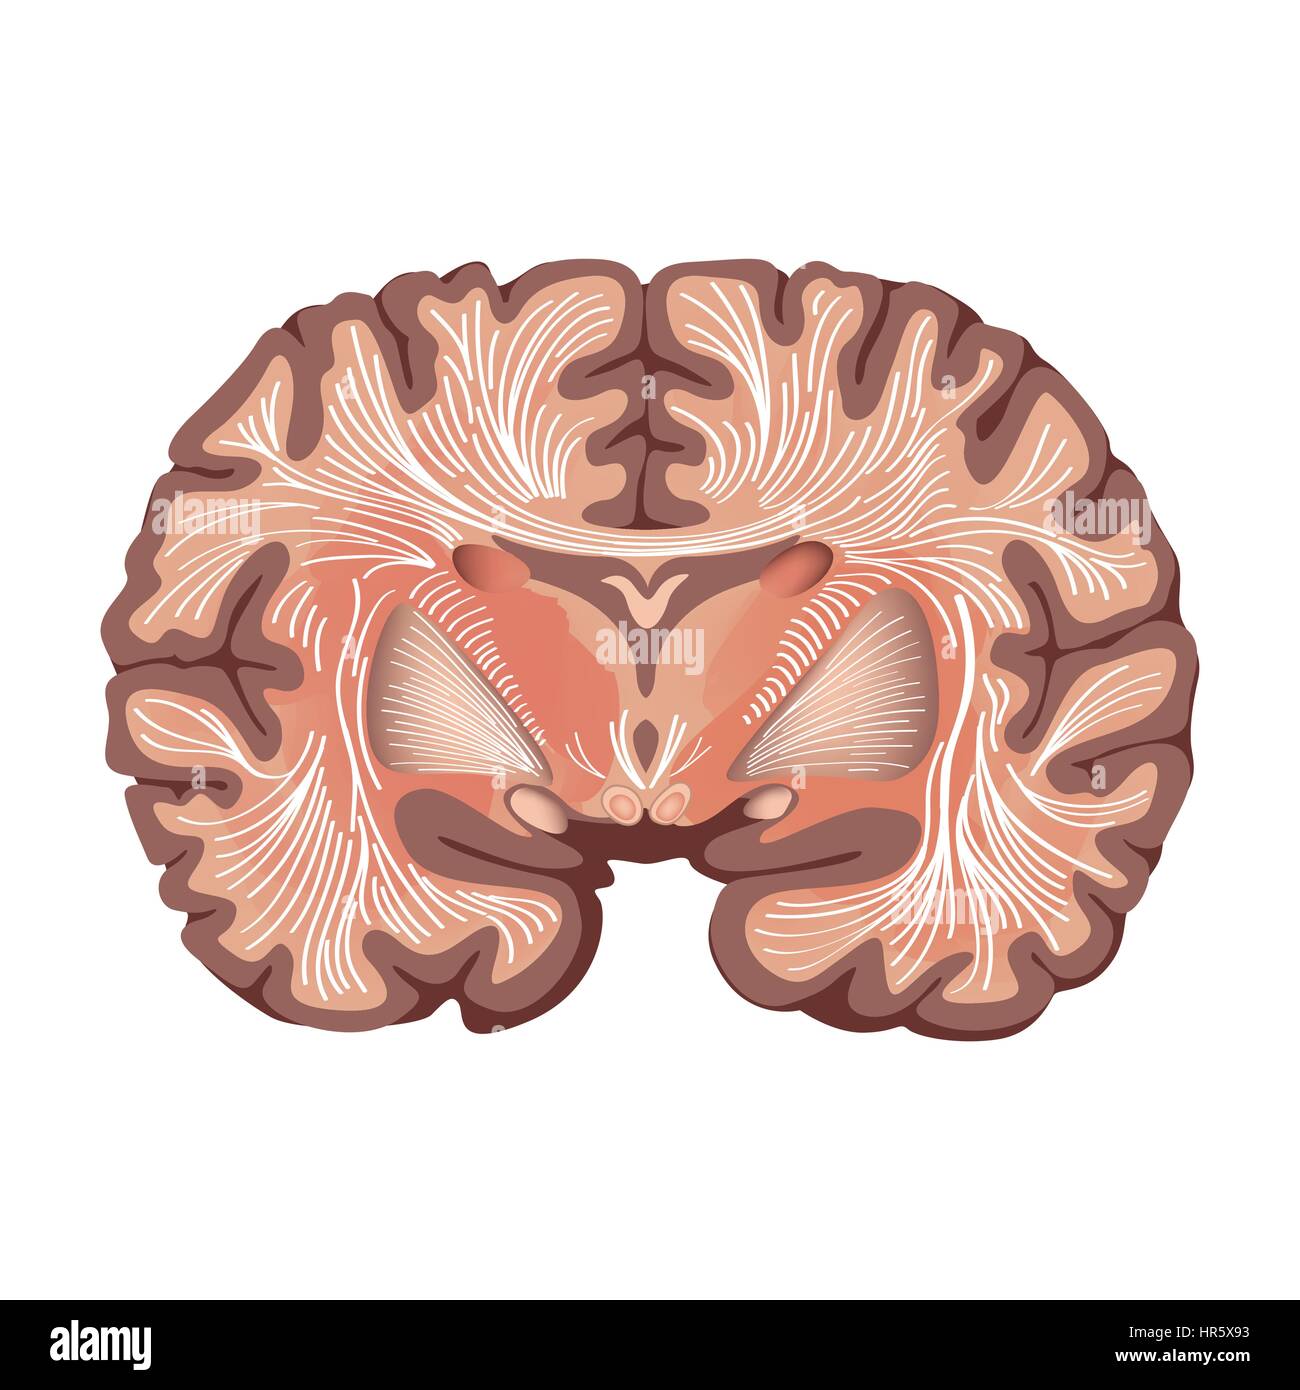

RFHR5X93–Anatomia cerebrale. cervello che mostra i gangli basali e nuclei talamico isolati su sfondo bianco.